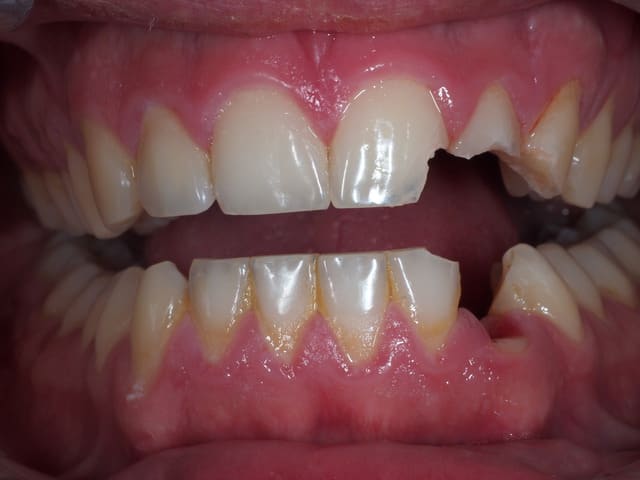

Coup de coude pendant un match de handball...